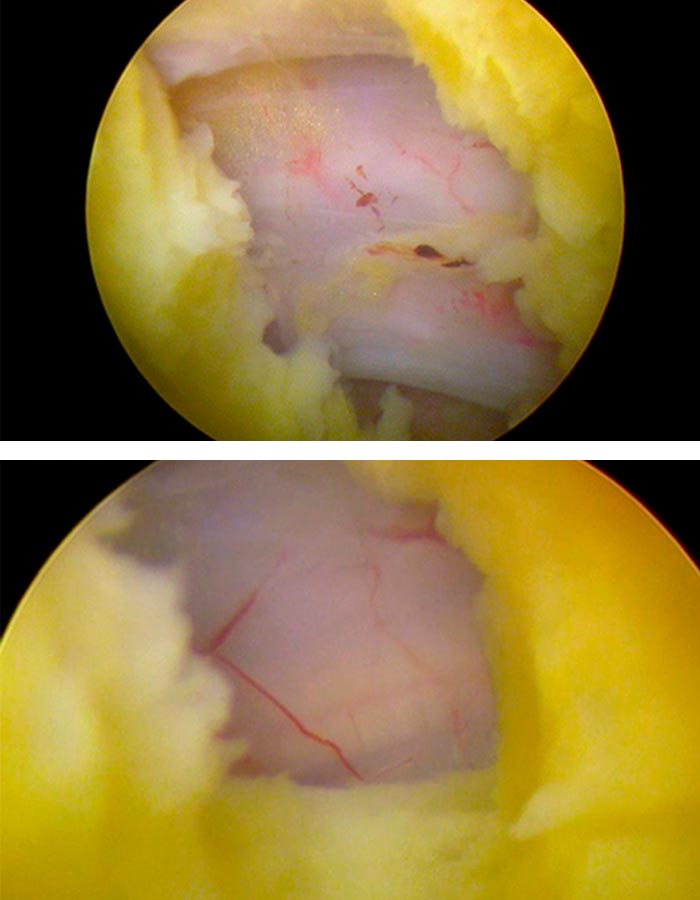

Comprobamos adecuadamente que todas las estructuras neurológicas han quedado descomprimidas y liberadas y gozan de buen riego bascular.